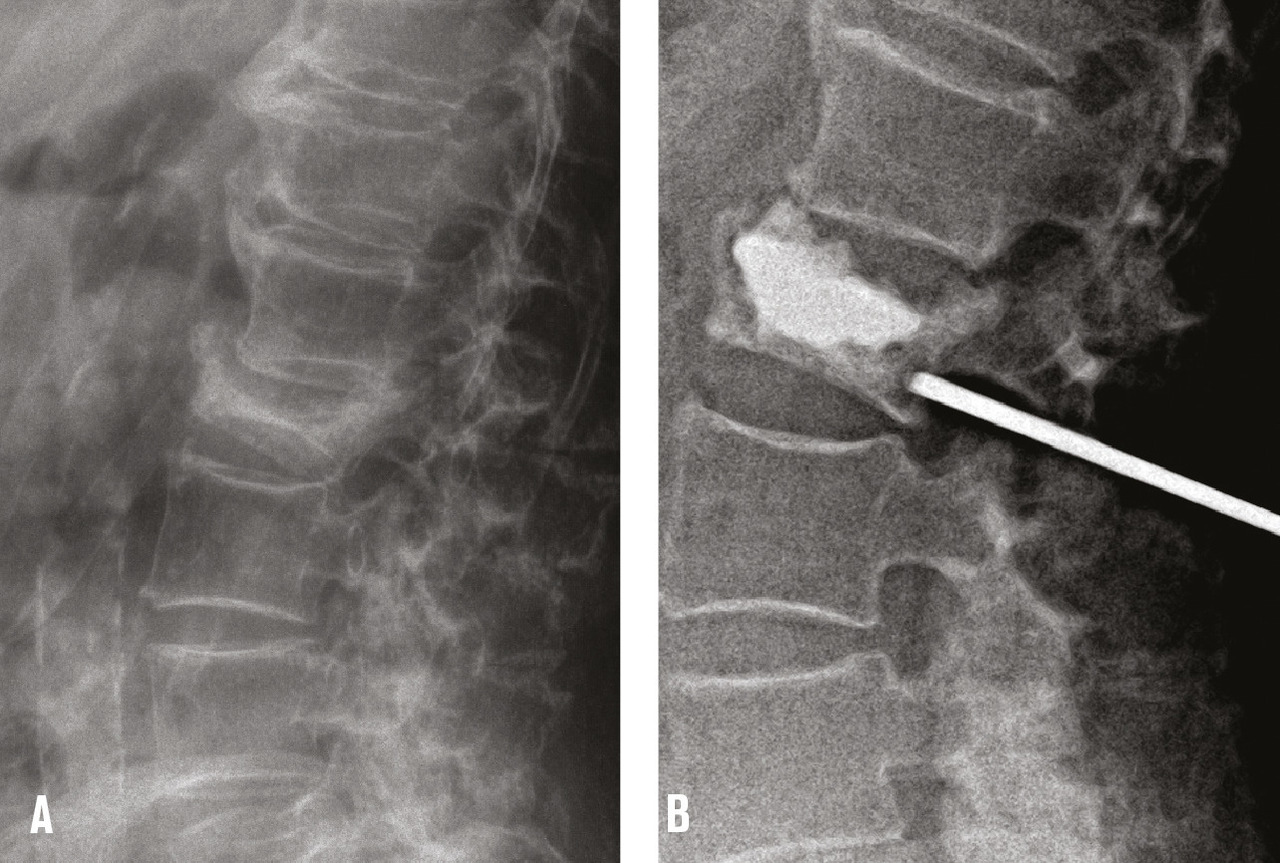

Dans la cyphoplastie, des ballonnets sont mis en place par voie transpédiculaire dans le corps vertébral fracturé, puis gonflés sous pression pour relever le plateau vertébral enfoncé et créer ainsi une cavité intracorporéale (fig. 2). Les ballonnets sont ensuite dégonflés et retirés et le ciment injecté à basse pression afin de remplir la cavité créée, ce qui diminue le risque de fuite extravertébrale de ciment. À côté de la cyphoplastie à ballonnets sont maintenant proposés de nombreux dispositifs de réexpansion vertébrale tels que des stents ou des « cricks » qui servent à repousser le plateau vertébral enfoncé mais sont laissés en place et « coulés » dans le ciment. Ils sont plus utilisés dans les fractures traumatiques ou malignes que dans l’ostéoporose. L’objectif de la cyphoplastie à ballonnets et de ces dispositifs est de réduire au moins partiellement l’angle de cyphose vertébrale qui est parfois important dans certaines fractures cunéiformes.